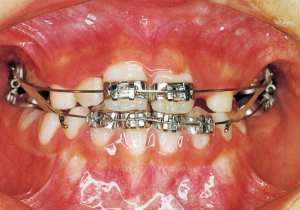

16 5-9-’92 After Phase 2 Treatment

17 8-15-’94 After Retention 14 years and 7 months after start of treatment

Retention period: 2 years 5 months

Total Management Period: 15 years from 8 years 1 month to 23 years 1 month

Reflecting on the course of treatment, one cannot help but marvel at the strength of the inherent biological program. At the same time, it makes one ponder how much artificial influence the body can allow and adapt to. While it would be difficult to say the long-term work in the first phase was suddenly meaningless, we must consider how much value it held for the overall treatment. The tongue is always positioned low due to its anatomical relationship within the facial structure. While it is understood that this low tongue position affects the dental arch, current treatment methods offer no solution. In such cases, we are acutely aware of the limited scope of what we can do.